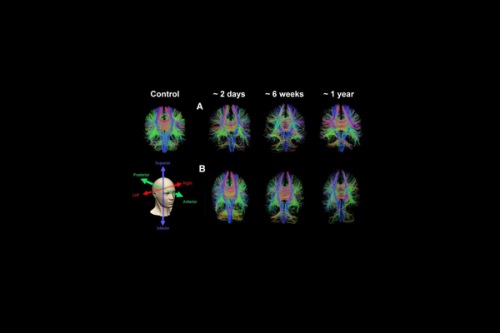

Dr. Newcombe and her team demonstrate that Diffusion tensor imaging (DTI) MRI, which measures the movement of water molecules in brain tissue to create detailed images of white matter tracts, can significantly improve the prognosis for concussion patients with normal CT scans.